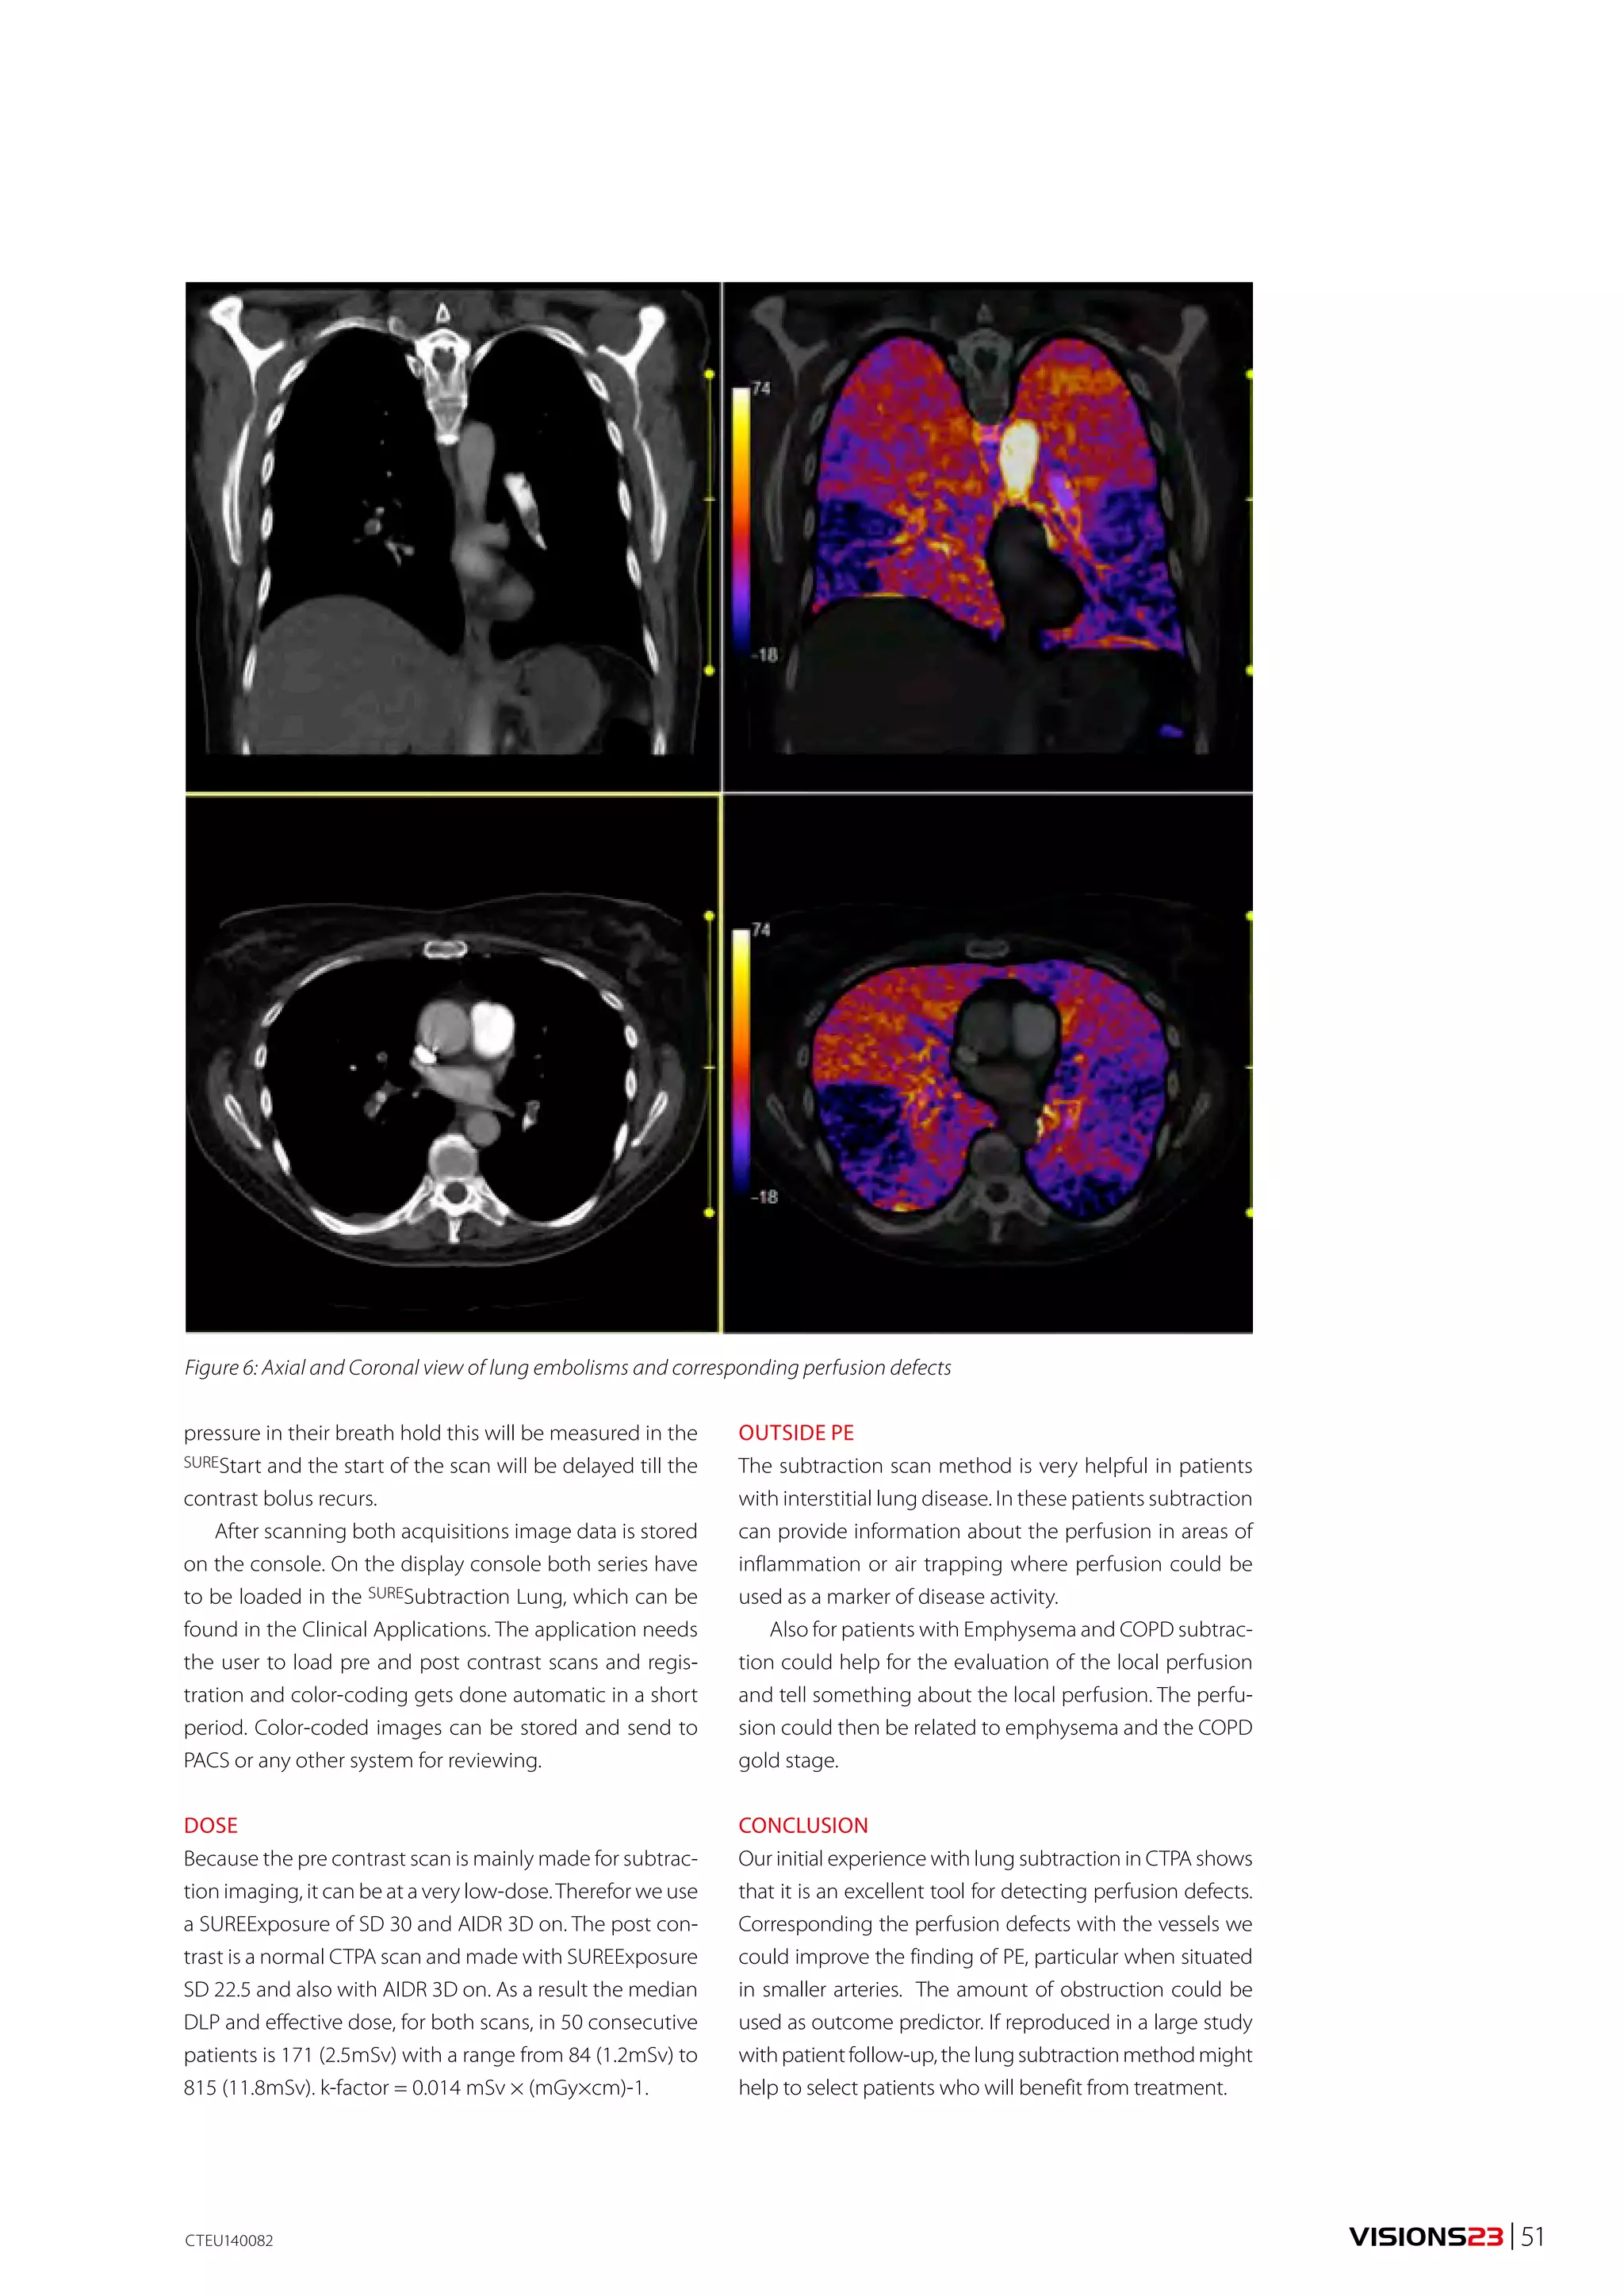

Figure 7: Comparison of virtual non-contrast images indicates that the SD and CNR are

improved with raw data based analysis.

is seen at the left cerebellopontine angle, but band-like

beam hardening artifacts are superimposed on the

tumor at the skull base. These artifacts could be reduced

by creating a monochromatic image at 70 keV while

maintaining good image quality.

A tumor at the left cerebellopontine angle and hydro-cephalus

associated with the tumor were confirmed by

MRI. The patient was referred to the neurosurgery depart-ment

of our hospital.

Best CNR image

This 75-year-old man visited a local physician complain-ing

of speech difficulties, headache, and vomiting. CT

showed a metastatic tumor in the left parietal region

surrounded by hemorrhage in the left parietal lobe.

Monochromatic images in the range from 35 to 135 keV

were created, and the image with the optimal CNR for

evaluating the tumor and cerebral parenchyma was gen-erated

using the Best CNR tool. The CNR values for each

keV are displayed as a graph. The Best CNR image for this